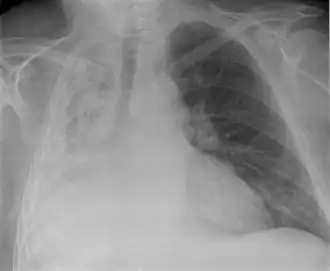

Bei der Perkussion hört man eine Dämpfung des Lungenschalls. Bei der Palpation besteht eine Abschwächung des Stimmfremitus.[3] Das Atemgeräusch ist bei der Auskultation der Lunge abgeschwächt. Im Röntgenbild des Thorax sind als direkte Zeichen eine Transparenzminderung und Verlagerung der Lappenspalten sowie als indirekte Zeichen ein Zwerchfellhochstand, eine Mediastinalverlagerung, ein kompensatorisches Emphysem, eine Hilusverlagerung und eine Engstellung der Rippen zu sehen. Differenzialdiagnostisch muss an eine Pneumonie gedacht werden, Atelektasen zeigen im Gegensatz zu dieser kein Bronchopneumogramm. Alternativ oder ergänzend zum Röntgenbild kann man eine Computertomografie-Aufnahme anfertigen. Im Ultraschall sieht man Atelektasen im Bereich eines Pleuraergusses als nicht belüftete, volumenverminderte Lungenabschnitte.